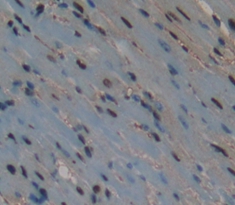

Polyclonal Antibody to Activating Transcription Factor 3 (ATF3)

- ApplicationsWB; IHC; ICC; IP.

The antibody is a rabbit polyclonal antibody raised against ATF3. It has been selected for its ability to recognize ATF3 in immunohistochemical staining and western blotting.

Immunohistochemistry: 5-20µg/mL;